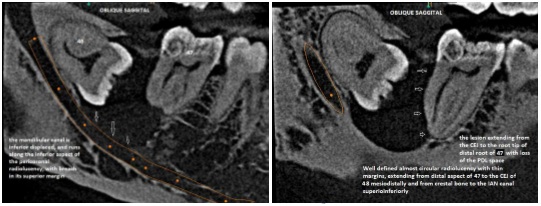

INVESTIGATIONS

Radiovisiography

Laboratories / Facilities